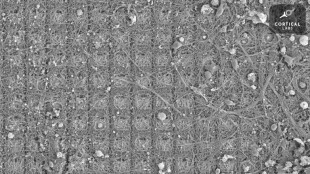

Des neurones doués de sensations ont appris à jouer à un jeu vidéo